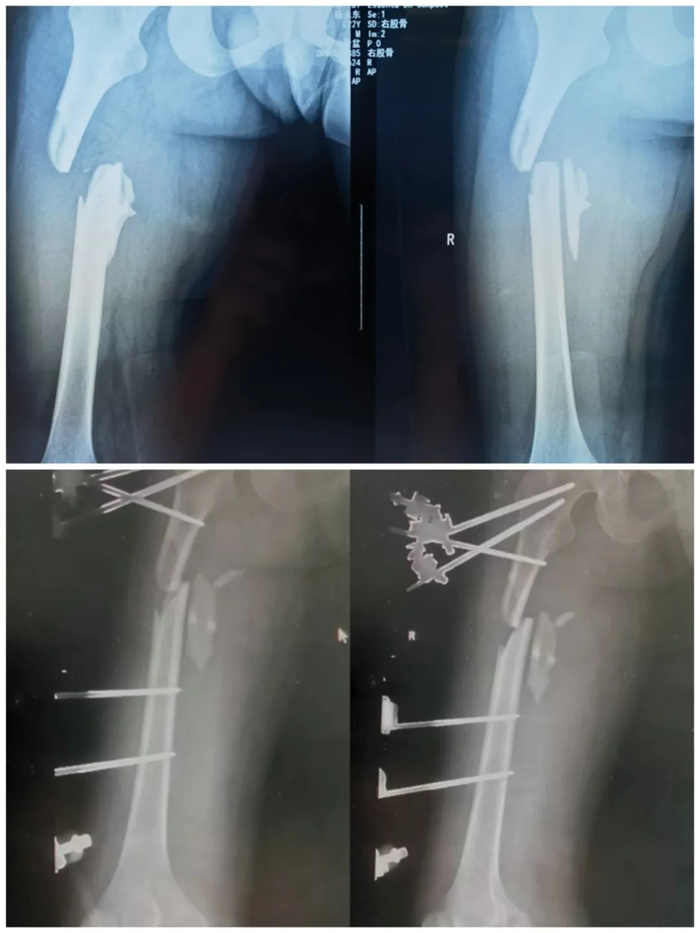

近日,一名22歲青年男性騎車不慎摔倒,右下肢損傷嚴(yán)重,被緊急送至我院。急診檢查發(fā)現(xiàn)患者右大腿明顯腫脹畸形,右側(cè)膝踝和足部活動受限,右下肢感覺麻木,血運(yùn)極差。初步診斷股骨干骨折合并右下肢神經(jīng)血管損傷。

創(chuàng)傷一科副主任楊錫明接到急診電話后,立即組織醫(yī)護(hù)團(tuán)隊(duì)準(zhǔn)備搶救,開通綠色通道并聯(lián)系血管外科急會診,給予患者完善術(shù)前相關(guān)檢查、備血、補(bǔ)充血容量并立即將患者送往手術(shù)室。經(jīng)探查發(fā)現(xiàn)患者腘窩處肌肉、筋膜、韌帶斷裂,股動脈遠(yuǎn)端及腘動脈無搏動、管壁無彈性,挫傷嚴(yán)重。血管外科主任徐存東組織科室人員立即行腘動脈切開探查,發(fā)現(xiàn)腘動脈內(nèi)有血栓,行取栓后血運(yùn)不佳,考慮動脈損傷嚴(yán)重,當(dāng)機(jī)立斷決定取同側(cè)大隱靜脈行血管移植。血管外科副主任李強(qiáng)沉著應(yīng)對,“取長補(bǔ)短”,使用血管縫合線將患者自體靜脈移植到動脈端。與此同時,創(chuàng)傷一科副主任劉志率領(lǐng)團(tuán)隊(duì)對患者一期實(shí)施股骨骨折閉合復(fù)位+右膝外固定架固定術(shù)。

經(jīng)過3個多小時的連續(xù)奮戰(zhàn),順利完成了腘動脈自體靜脈搭橋移植術(shù)+患肢外固定支架固定術(shù)?;颊哂蚁轮┙K于恢復(fù),手術(shù)順利結(jié)束。術(shù)后又經(jīng)過ICU、普通病房的精心治療護(hù)理,目前患者肢體恢復(fù)良好,無明顯并發(fā)癥,已康復(fù)出院。